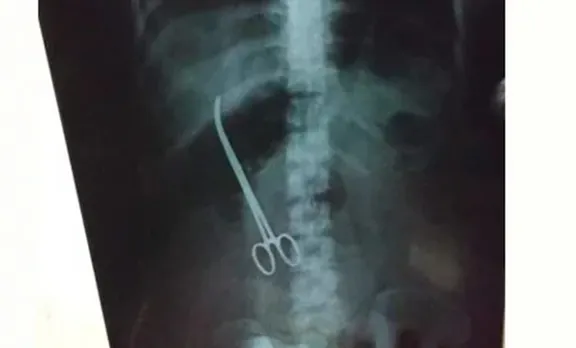

യുവതിയുടെ വയറ്റില് ഡോക്ടര്മാര് കത്രിക വെച്ച് മറന്നു; പുറത്തെടുത്തത് മൂന്ന് മാസം കഴിഞ്ഞ്

/indian-express-malayalam/media/media_files/uploads/2019/02/Forceps-cats-002.jpg)